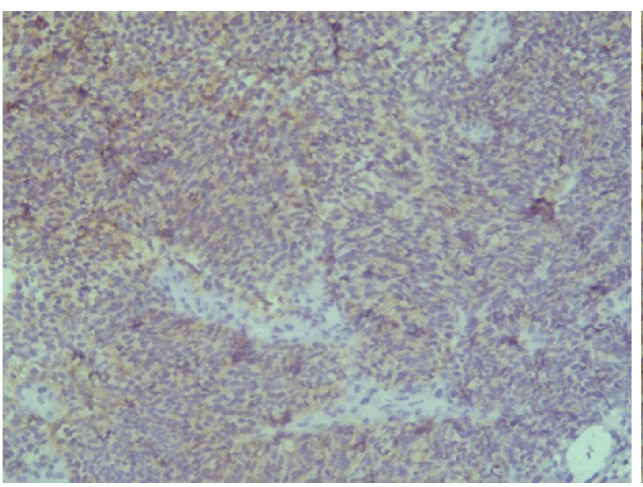

Отрицательная экспрессия была отмечена в диагностических образцах с использованием антител к Keratin.Pan, CD45, p63, S100, EMA (E29), TTF1(рис. 7–12).

Рис. 7. Keratin.Pan [AE/AE3] ×200

Рис. 8. CD 45 [Cocktail] ×200

Рис. 9. p63 [7JUL] RTU ×200

Рис. 10. S100 ×200

Рис. 11. EMA [E29] ×200

Рис. 12. TTF1 [8G7G3/1] ×200